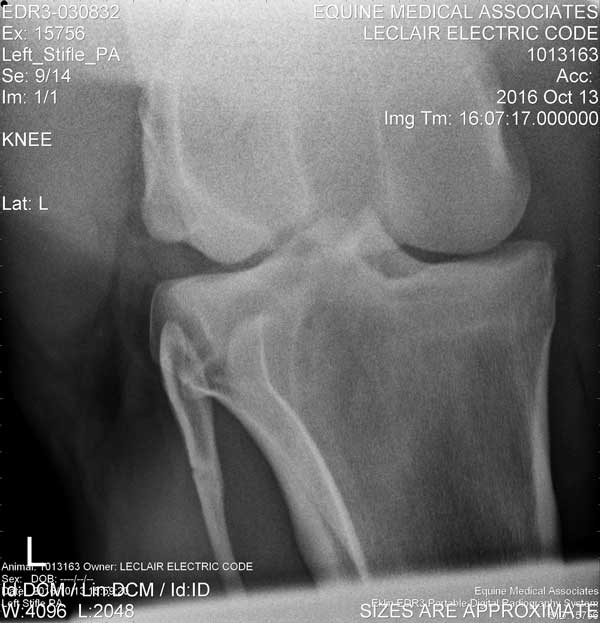

Stifle

Left